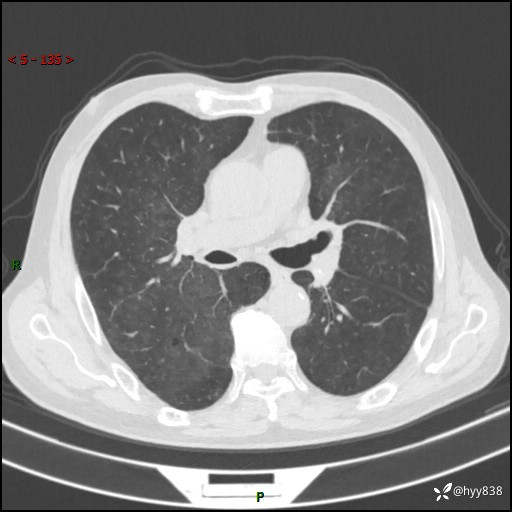

儿女怕老人寂寞,养了两只鹦鹉,呼吸科主任问我典不典型---结果公布~

武医生 等 4 位达人已点赞患者性别:男

患者年龄:71岁

主诉:喘气半年余,咳嗽乏力伴味觉减退2月余

简要病史:者半年前左右无明显诱因出现呼吸困难,轻微运动后出现喘气,未予以重视。2月余前受凉感冒后出现咳嗽,咳白色泡沫痰,不易咳出,于当地医院行输液治疗,未见明显好转,并感觉全身乏力,体力下降,并感口苦,味觉减退。近10余天前感咳嗽喘气加重,咳白色泡沫痰,不易咳出,口苦,味觉减退加重。为进一步检查及治疗,入我院就诊,门诊以“呼吸困难”收入院治疗。 起病以来,患者精神,睡眠,饮食欠佳,大小便可,体力下降明显,体重稍下降。

辅助检查:CT

临床诊断:呼吸困难

讨论:诊断?

胸部CT平扫